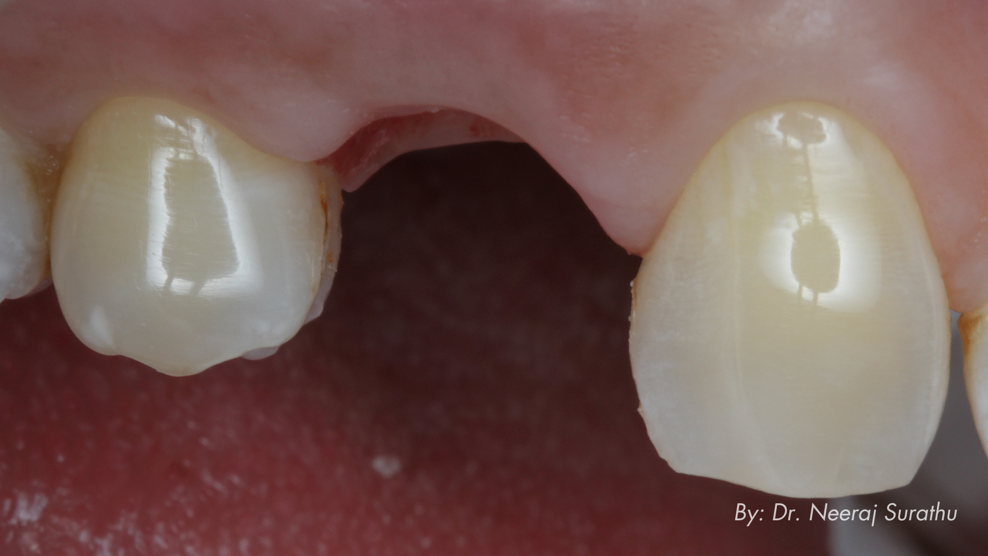

To ensure an ideal emergence profile, implant positioning and intended emergence were meticulously planned using specialised software. A 3D-printed surgical guide enabled pinpoint precision during implant placement (Fig. 8).

Intra-oral scans of the patient’s preoperative condition and the tooth shape from the CBCT scan were utilised to recreate the restorative profile. This process allowed for the fabrication of a 3D-printed shell that closely replicated the original profile (Figs. 9 & 10). This shell was characterised using a stain and glaze system (Rodin Palette Naturalizing Kit, Pac-Dent) to harmonise with the aesthetics of the adjacent teeth. By creating the ideal profile, the soft tissue was adequately supported, preventing any loss of papillary height or soft-tissue contour changes (Fig. 11).

Fig. 9: 3D-printed characterised shell provisional restoration with a vertical stop to guide intra-oral chairside pick-up.

Fig. 10: Intra-oral chairside pick-up of the 3D-printed shell provisional restoration.

Fig. 11: 3D-printed shell picked up using flowable composite and ready to deliver on the day of surgery.